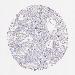

OVARIAN CANCER - Protein expressioni

A mouse-over function shows sample information and annotation data. Click on an image to view it in a full screen mode. Samples can be filtered based on level of antibody staining by selecting one or several of the following categories: high, medium, low and not detected. The assay and annotation is described here.

Note that samples used for immunohistochemistry by the Human Protein Atlas do not correspond to samples in the TCGA dataset.

Antibody stainingi

Antibody staining in the annotated cell types in the current human tissue is reported as not detected, low, medium, or high, based on conventional immunohistochemistry profiling in selected tissues. This score is based on the combination of the staining intensity and fraction of stained cells.

Each image is clickable and will lead to virtual microscopy that enables deeper exploration of all samples and also displays staining intensity scores, fraction scores and subcellular localization as well as patient and tissue information for each sample.

Antibody HPA003134

Cystadenocarcinoma, mucinous, NOS

Carcinoma, endometroid

Cystadenocarcinoma, serous, NOS